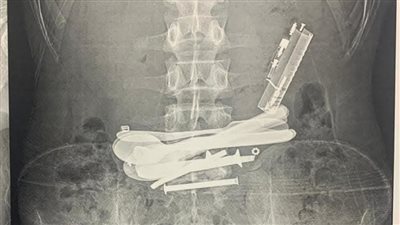

ولاعات ومقصات وسبح.. إنقاذ مريض ابتلع أجسامًا معدنية بمستشفى سوهاج الجامعي

الثلاثاء 18/03/2025 07:26 م